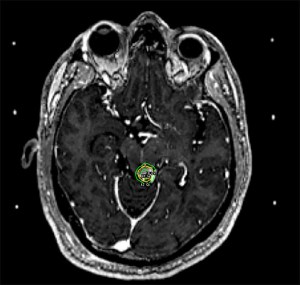

In summary, the role of SRS for meningioma is varied and may include definitive management for small or unresectable tumors, adjuvant treatment to address the remnant of a planned subtotal resection or high grade tumors, or as a salvage for late recurrences. An example of an SRS treatment following subtotal resection for a WHO Grade I meningioma is illustrated in Figure 3. Clinical decision making should be shared between the patient, radiation oncologist, and neurosurgeon and take into consideration tumor size, location, grade, prior surgery, and patient preference in order to achieve optimal care (60).